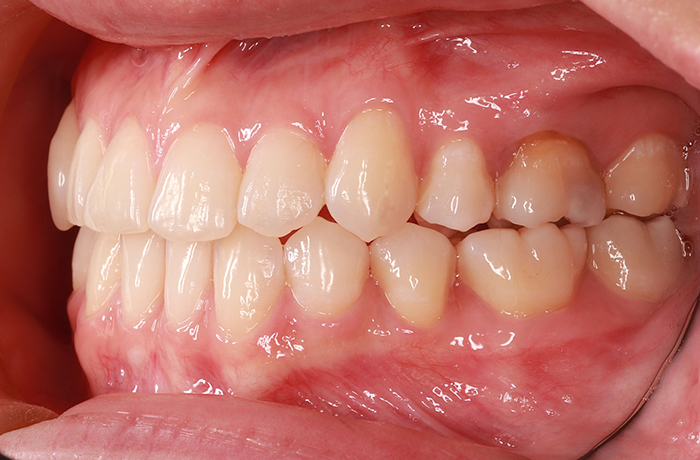

I様

治療前

年齢 34歳

性別 男性

治療名称 マウスピース型カスタムメイド矯正歯科装置(インビザライン)・コンプリヘンシブパッケージ(フルパッケージ)

総額治療費用 770,000円(税込) 金額備考 検査・診断料33,000円含む

治療期間 8か月 通院頻度など 40日ごと

患者の症状 上顎前歯の凸凹

治療方法 非抜歯で、マウスピース型カスタムメイド矯正歯科装置による矯正

治療結果 歯並び、咬み合わせが良くなりました。

その他治療に関する情報 歯並びをより良くするために追加でアライナーを発注しました。

リスク/副作用 スペース不足を解消するために歯と歯の間をわずかに削合しました。